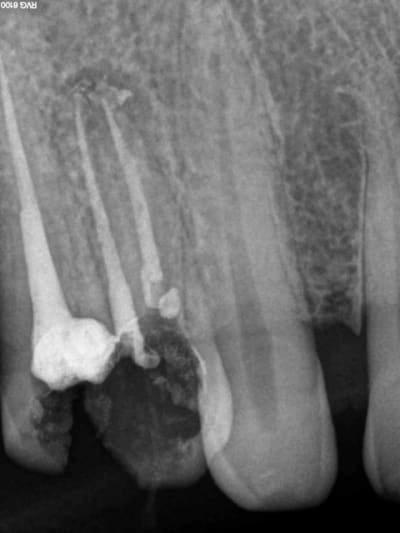

Aujourd'hui patient en urgence ca tombe bien pour une fois synchro avec un lapin.

45 mn de turbinage intensif 2 endos + 2 SC 33; On cote comment les radios ?

Z6, SC 20, Z3,Z3, SC20, Z3, Z3, SC 33, Z3, SC 33, Z3 ?